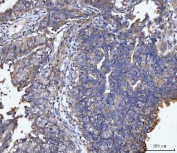

IHC staining of FFPE human ovarian carcinoma tissue with MUC1 antibody. HIER: boil tissue sections in pH8 EDTA for 20 min and allow to cool before testing.